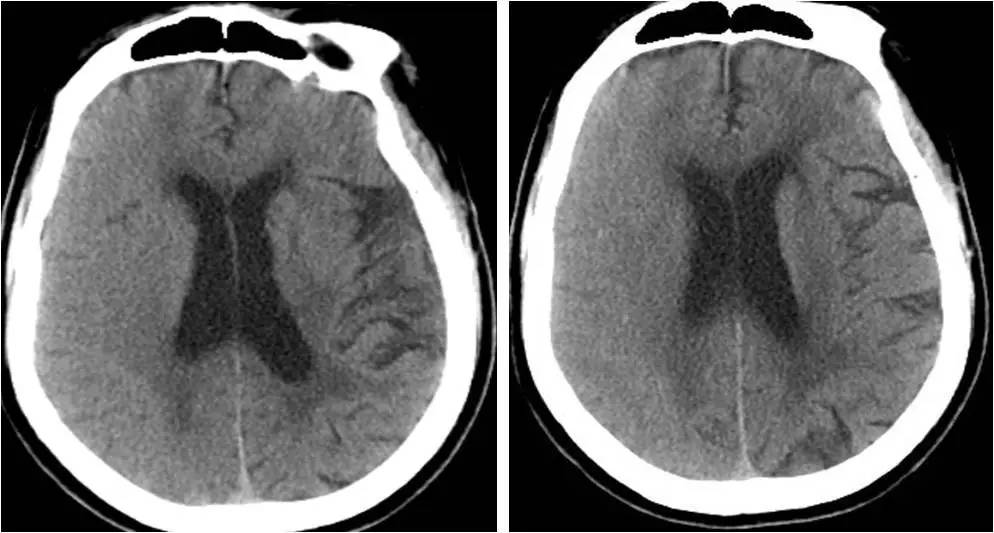

》术后6小时,出现左侧肢体无力,无头痛,无恶心、呕吐;

》查体:嗜睡态势,双眼向右凝视,左上肢肌力0级,左下肢肌力Ⅲ级,肌张力稍低,感觉正常,病理征阴性;

》心电监护示:心率 82次/分,血压 120/60mmHg,血氧饱和度 97%。

复查DSA,右侧颈内动脉起始部支架定位良好,支架内血流通畅,右侧大脑中动脉显影无异常。

诊断